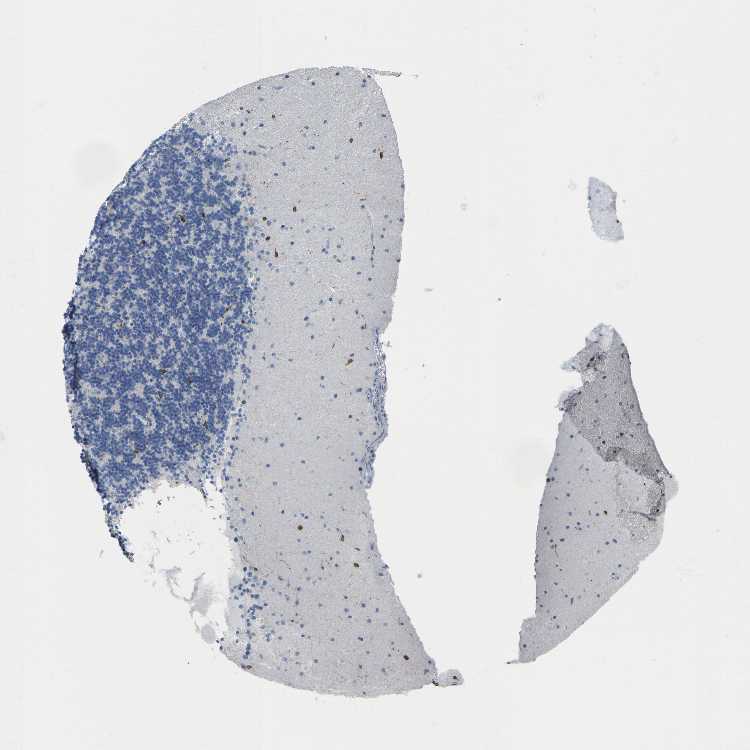

BRAIN CEREBELLUM Show tissue menu

CEREBELLUM - Expression summary

CEREBELLUM - Antibody stainingi

Antibody staining in the annotated cell types in the current human tissue is reported as not detected, low, medium, or high, based on conventional immunohistochemistry profiling in selected tissues. This score is based on the combination of the staining intensity and fraction of stained cells.

Each image is clickable and will lead to virtual microscopy that enables deeper exploration of all samples and also displays staining intensity scores, fraction scores and subcellular localization as well as patient and tissue information for each sample.

Antibody HPA002834Antibody CAB020315

Purkinje cells Not detectedNot detected

Cells in granular layer LowLow

Cells in molecular layer LowMedium